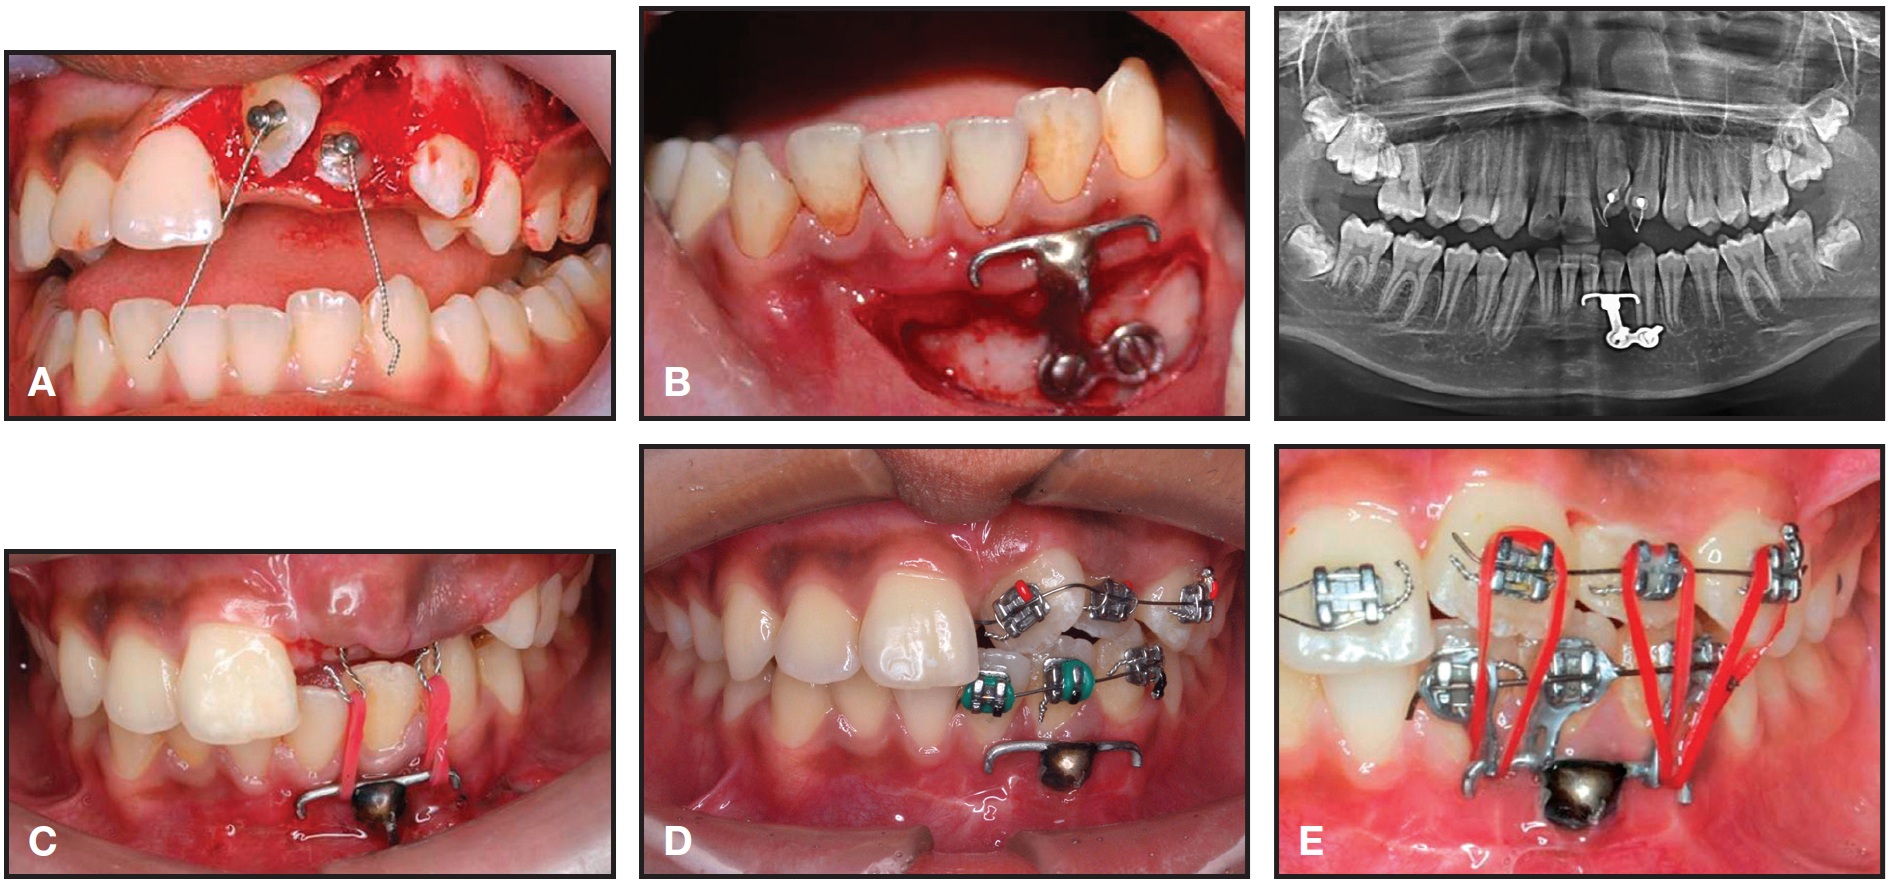

The three supernumerary teeth were extracted, and the impacted teeth were surgically exposed. After a full-thickness mucoperiosteal flap was raised for the central and lateral incisors, buttons were bonded to their labial surfaces for closed eruption. An apically repositioned flap was raised for the canine (Fig. 2A).

An "L"-shaped miniplate was modified by soldering it to an .035" stainless steel wire with hooks for attachment of elastics, then inserted into the lower anterior region below the root apices (Fig. 2B).17,18 An extrusive force of about 55g was applied to the incisors with 3/16" red elastics* (Fig. 2C). Six months later, when the teeth had erupted adequately, the upper and lower left anterior segments were bonded with .022" MBT**brackets and sectional wires were placed for alignment (Fig. 2D). Another 12 weeks later, elastic traction was added from the miniplate to the supraerupted lower left incisors and canine, applying an intrusive force of 15g (Fig. 2E).

Fig. 2 A. Attachments bonded to surgically exposed incisors. B. Miniplate placed in lower anterior region below root apices. C. Traction of unerupted incisors using red elastics attached to “pigtail” hooks. D. After six months of traction and bonding of upper and lower left anterior teeth with sectional wires. E. Traction added to overerupted lower left incisors and canine.